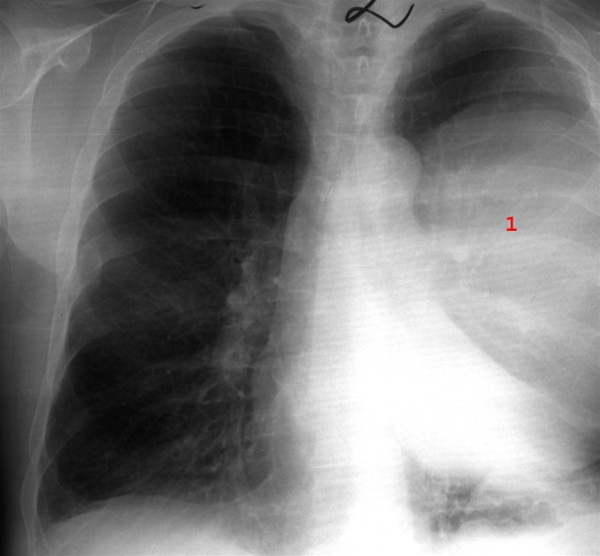

Stor lungeabsces, pusfyldt hulrum i lungevævet (1), set fra siden.